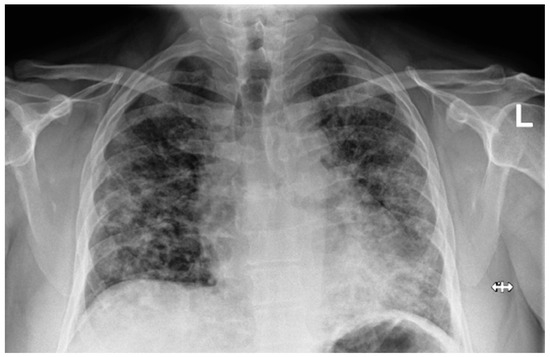

After being discharged, at the one-month follow up, the patients were generally feeling much better, were more rested and their daytime sleepiness was reduced; dyspnea on exertion was still troubling several of them. The memory card showed significantly lower AHI per hour in all of them and the device was used over 90% of the time, except for one patient, who used it 68.7% of the time. CPAP therapy was generally well tolerated. Spirometry was normal in five patients and in two patients a restrictive ventilatory defect was noticed, most likely caused by obesity or due to leftover post-COVID infiltrations in the lungs. The ABG analysis was normal in five patients, although in two patients hypoxemic respiratory failure remained. The diffusion capacity for carbon monoxide (DLCO) was reduced (<70%) in four patients and was normal (>70%) in three patients. A chest X-ray described either a partial or complete regression of bilateral lung infiltrates (Figure 5). In two patients, CPAP parameters were slightly adjusted, and in others were left as they were initially prescribed. All follow-up parameters are shown in Table 4.

Figure 5. Chest X-ray at the follow up: patient 5. Partial regression of bilateral lung infiltrates (the “L” orientation marker indicates the left side).